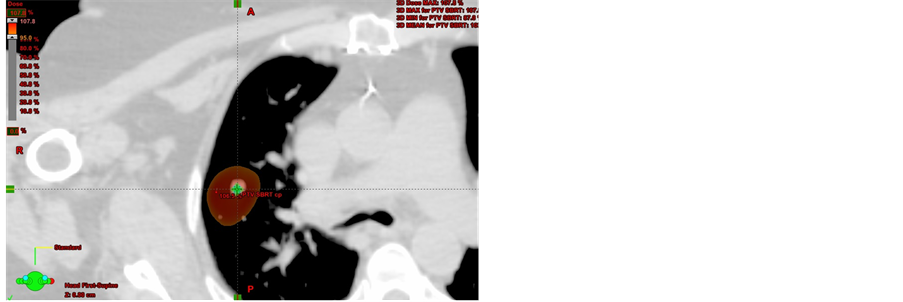

Data from thirty-nine patients who underwent SBRT lung treatment were used for this study (Figure 3(a), Figure 3(b)).

Their prescribed doses were either 5 daily fractions of 10 Gy or 4 daily fractions of 12.5 Gy, for a total dose of 50 Gy using SBRT. The patient characteristics are summarized in Table 1.

Figure 3. A 70-year-old woman with lung cancer was treated with SBRT for a total dose of 50 Gy given in 5 fractions.